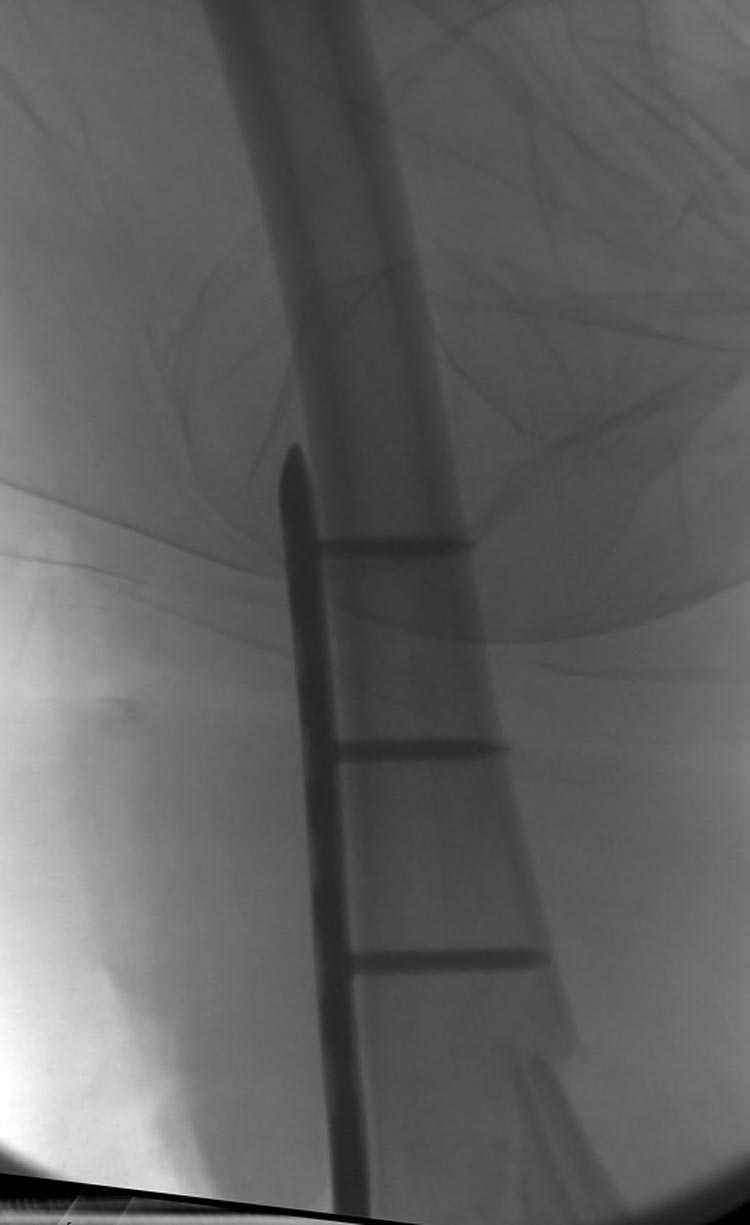

[Ortho] Дистальный перелом бедра

Поэтому такие меж и над- мыщелковые переломы более предпочтительным считается фиксировать мыщелковыми пластинами

Устанавливается из малого разреза "не вскрывая сустав" со стороны латерального мыщелка, и Insertion Jig позволяет установить пластину "мостовидно" перкутанно в проксимальном отделе, "не вскрывая и не трогая" место перелома.

Имя     : distal femur crm 3.jpg